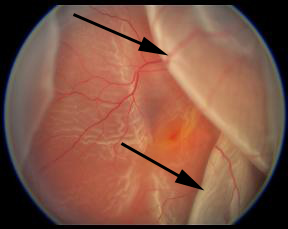

Resim 1: Retina dekolmanı olan hastanın gözdibi fotoğrafı. Retinanın olması gereken yerden ayrıldığı, öne doğru geldiği, yer yer üst üste katlandığı görülmektedir. Retinanın normal pembe rengini kaybettiği, daha opak (beyaz) hal aldığı izlenmektedir (siyah oklar).